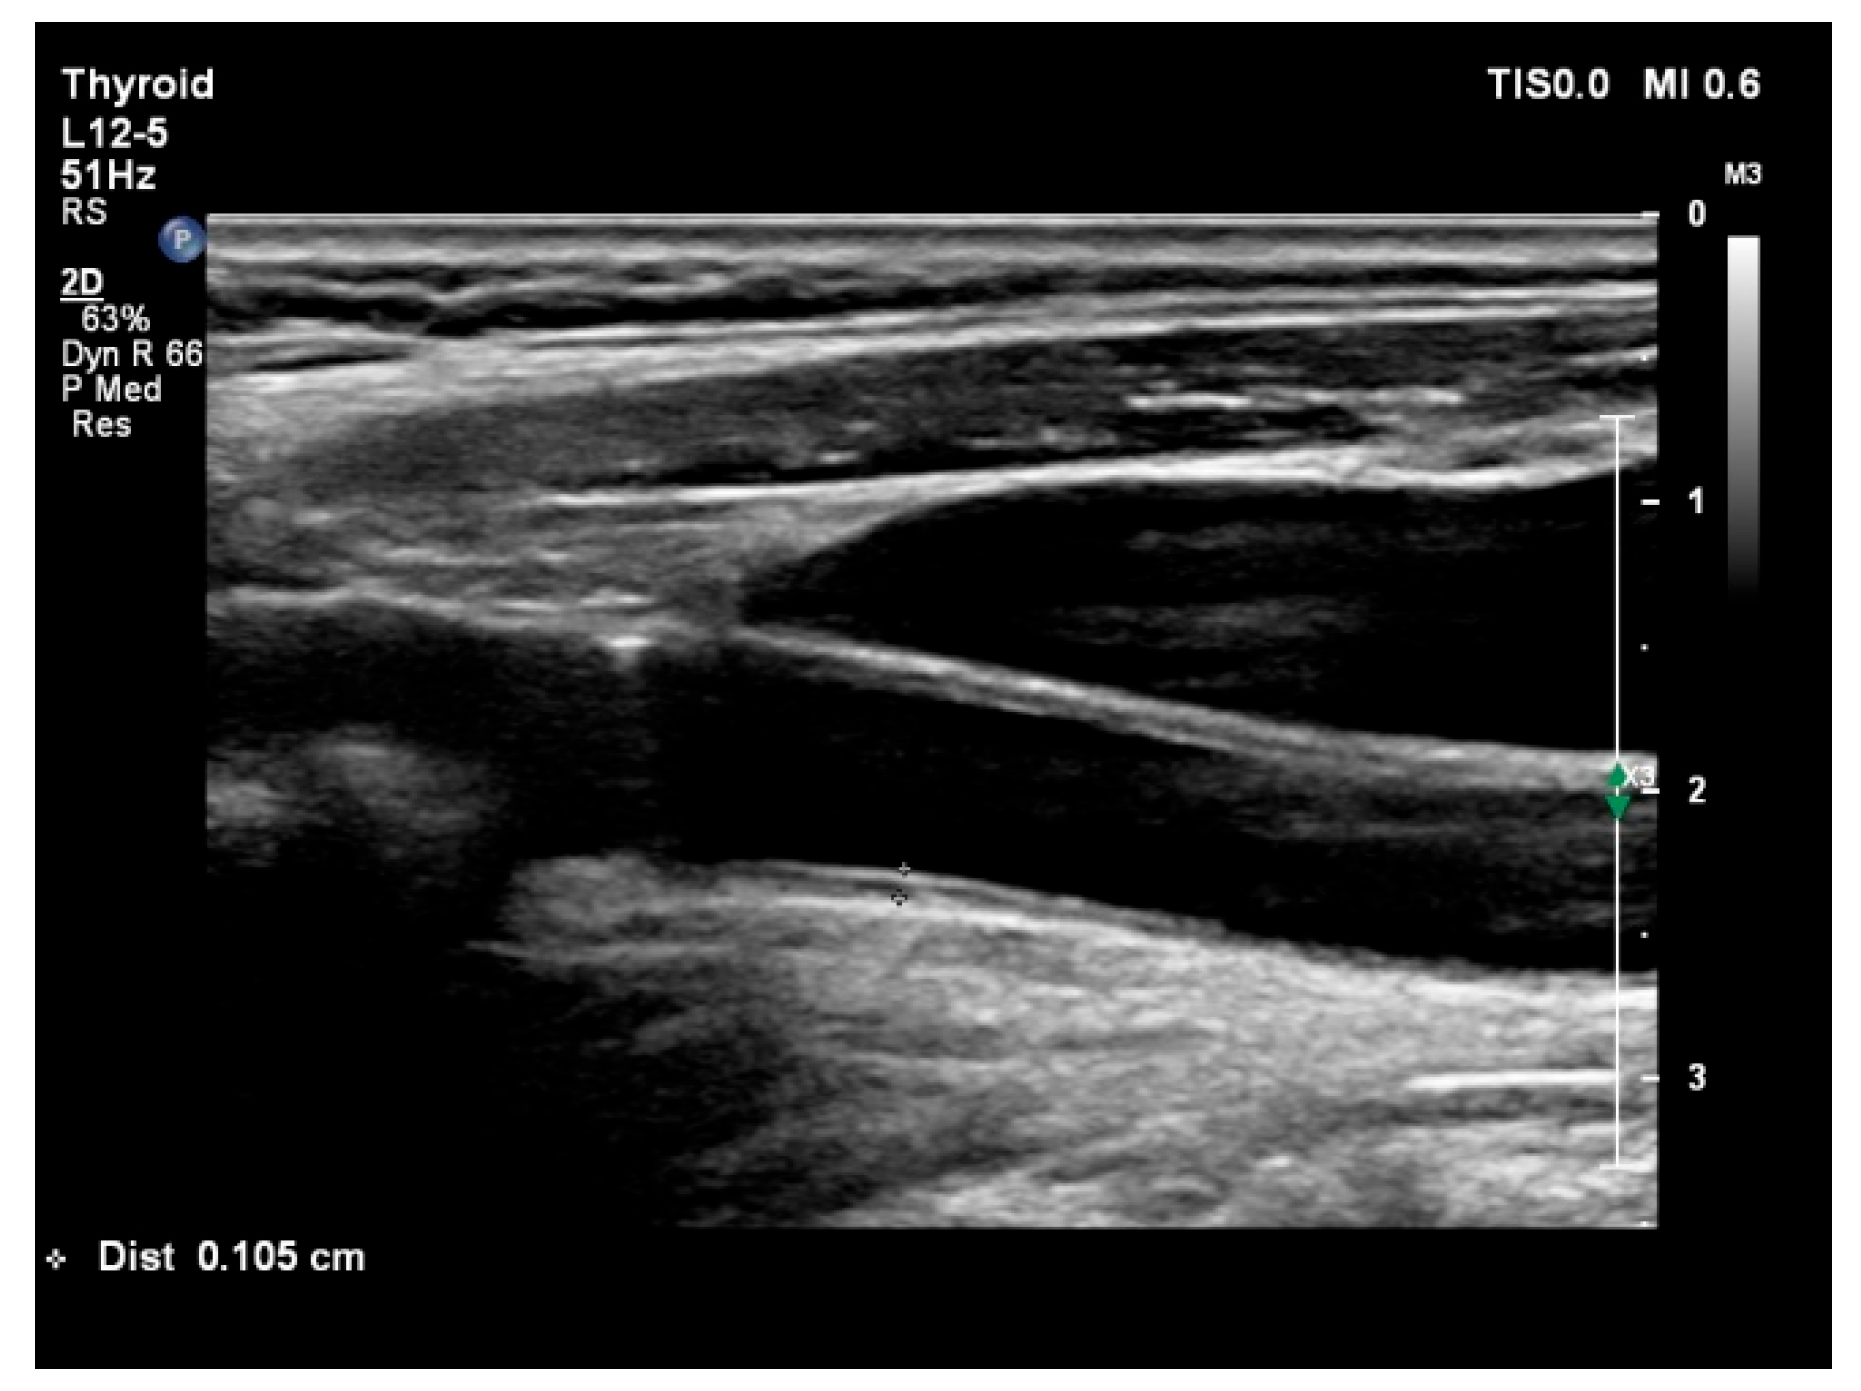

2.3. Coronary Angiography and B-Mode Ultrasound Examination

| Carotid IMT (mm) | 0.81 ± 0.21 | 0.71 ± 0.17 | <0.001 |